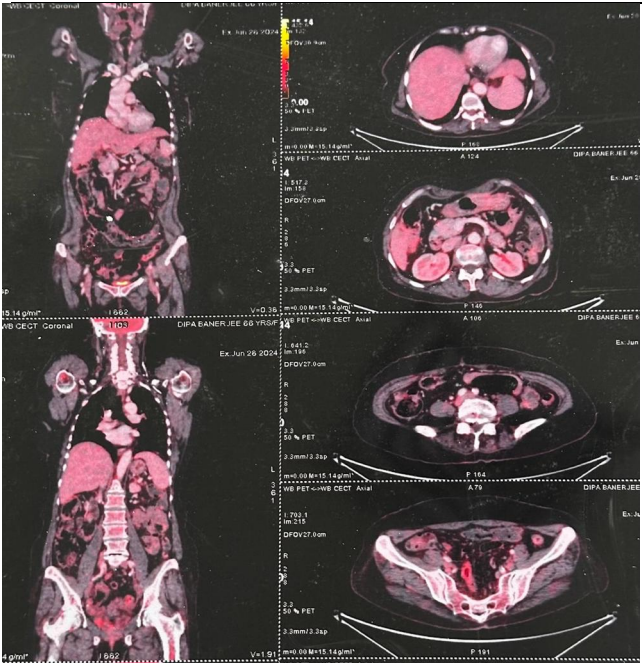

Fig 2

First-line Therapy: The patient received six cycles of Cisplatin and Etoposide, leading to a significant response as noted on interim PET-CT scans [Fig 2]. However, disease progression was observed post-treatment.

Figure 2